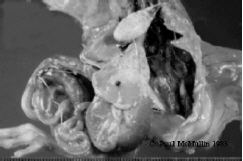

- Chalky white deposits on pericardium, liver, air sacs, peritoneum.

- Similar deposits may be present in joints and are usually present in the kidney.

| Figure 36. Severe visceral gout in a young chick. There are white chalky deposits around the heart (in the pericardium) on all major abdominal organs, including liver, gizzard and intestines, and even in the tissues of the thigh. |